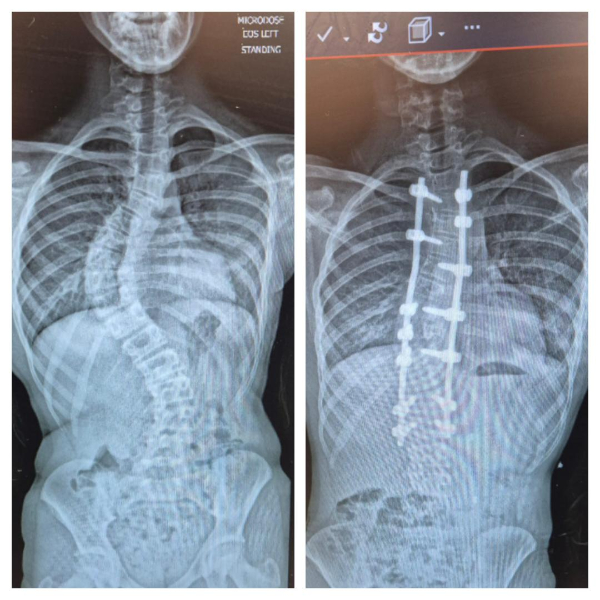

Following Emily's diagnosis of scoliosis in May 2023, she was immediately under the care of the amazing staff at Sheffield Children's Hospital. Having discovered the extent of the curve in her spine, she was told that bracing was the best (only) option to try to correct it. She opted to take part in a clinical trial to support their research into better bracing methods and was incredibly well cared for over the next 18 or so months.

Unfortunately her scoliosis progressed to a stage where an operation was the only option, and she underwent spinal surgery in March this year. The care she received was amazing and she walked out of SCH 3 days later to start her recovery. We're so grateful for the support we received from the hospital. We're doing this fundraiser to raise some cash for a brilliant organisation and to say thanks for everything.